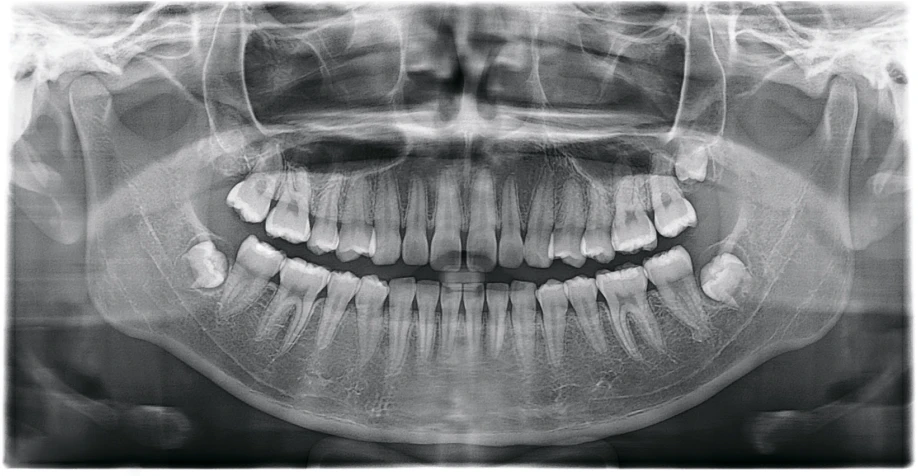

Изображения с высоким разрешением для точной диагностики

Получите исключительную чёткость изображения и настраиваемый объём сканирования с помощью RAYSCAN. Адаптируйте свои снимки в соответствии с вашими конкретными клиническими потребностями, и будьте уверены в том, что запечатлеете каждую сложную деталь и раскроете безграничные возможности.

FOV 18×16 см, 300 μm

FOV 10×10 см, 160 μm

FOV 4×5 см, 70 μm

Технология AMF (Адаптивный движущийся фокус) выбирает оптимальный слой изображения для получения чётких панорамных изображений, что позволяет легко определить состояние пародонта пациента и локализацию поражения.